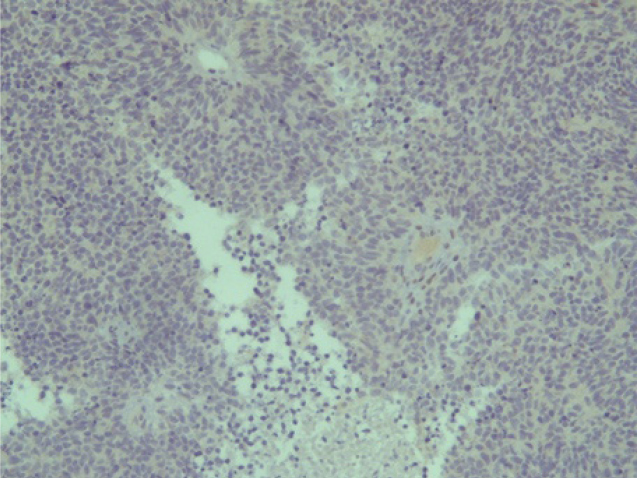

Поэтому при первичном гистологическом исследовании диагноз эстезионейробластомы был установлен только у 6 пациентов (66,6 %), у троих больных (33,4 %) были диагностированы другие формы злокачественного процесса, что не соответствовало клиническим проявлениям. Во всех случаях проводили иммуногистохимическое (ИГХ) исследование. ИГХ-исследование проводили на срезах с парафиновых блоков с использованием антител к Keratin.Pan (AE/AE3), CD45 (Cocktail), Synaptophysin (SP11), ChromograninA (SP12), CD56 (56C04), Ki-67 (30-9), p63 (7JUL)RTU, S100, INI1, CD99 (HO36-1.1). Также выполняли доставку с антителами к EMA (E29), TTF1 (8G7G3/1). В диагностических материалах была отмечена положительная экспрессия Synaptophysin, ChromograninA, CD56, Ki-67 (до 90% ядер), INI1 (рис. 2–6).

Отрицательная экспрессия была отмечена в диагностических образцах с использованием антител к Keratin.Pan, CD45, p63, S100, EMA (E29), TTF1(рис. 7–12).

Рис. 2. Synaptophysin [SP 11] ×200

Рис. 3. Chromagranin A [SP 12] ×200

Рис. 4. CD 56 [56C04] ×200

Рис. 5. Ki-67 [30-9] (90%) ×200

Рис. 6. INI 1 ×200

Рис. 7. Keratin.Pan [AE/AE3] ×200

Рис. 8. CD 45 [Cocktail] ×200

Рис. 9. p63 [7JUL] RTU ×200

Рис. 10. S100 ×200

Рис. 11. EMA [E29] ×200

Рис. 12. TTF1 [8G7G3/1] ×200

Эти результаты иммуногистохимического исследования подтверждают наибольшее соответствие иммунофенотипа опухоли – ольфакторной нейробластоме (G3 по Hyams) М9522/33.